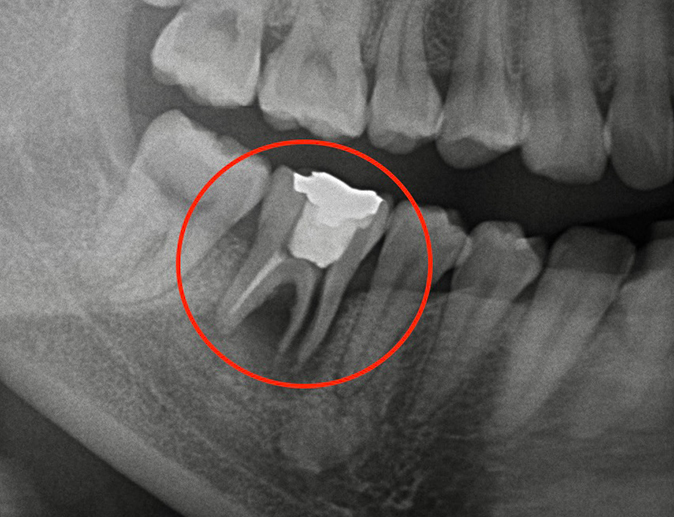

デメリット⑥ 歯根破折による抜歯のリスク

ブリッジの土台となる歯には継続的に過度な負担がかかるため、歯根破折を起こすリスクがあります。歯根破折とは歯の根にひびが入ったり、割れたりする現象で、一度破折すると抜歯が避けられないケースがほとんどです。神経をすでに除去した歯を土台とする場合、弱くなった歯にさらに負担をかけることになるため、歯根破折のリスクが高まります。

【歯根破折の症例写真】

ブリッジ治療のリスクをご理解いただいた上で、インプラント治療との比較検討をされている方も多くいらっしゃいます。インプラント治療では隣接する健康な歯を削る必要がなく、歯根破折のリスクも避けられます。ブリッジとインプラント治療で悩まれている方は、ぜひ一度当院でご相談ください。